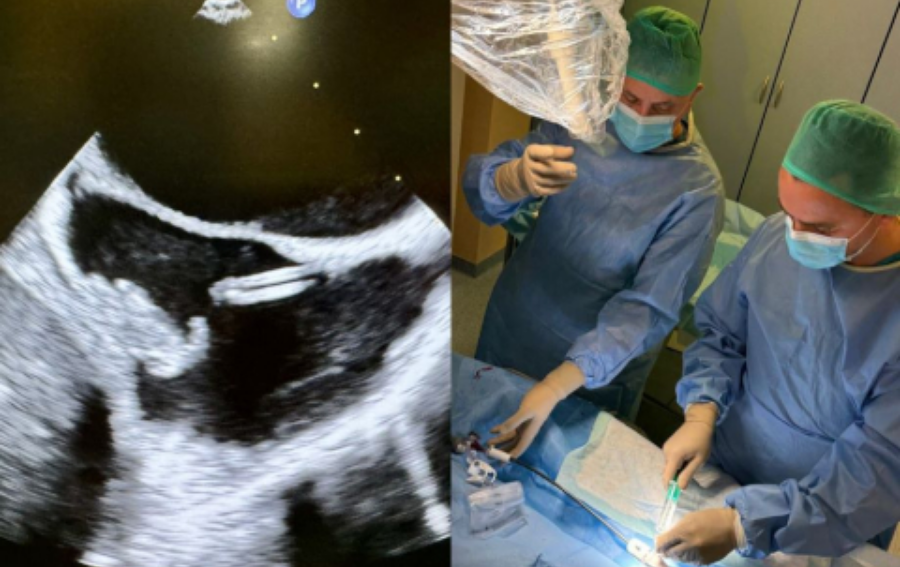

W Klinice Chirurgii Ogólnej, Transplantacyjnej i Wątroby UCK WUM, zespół pod kierunkiem prof. Michała Grąta, przeprowadził pierwsze na świecie przeszczepienie wspomagające wątroby u chorej po urazie własnego narządu w wyniku wypadku komunikacyjnego. Dzięki wykorzystaniu zdolności regeneracyjnych pozostałego fragmentu własnej wątroby chorej, przy czasowym wsparciu przeszczepionego fragmentu wątroby zmarłego dawcy, 50-letnia pacjentka uniknęła transplantacji całego [...]